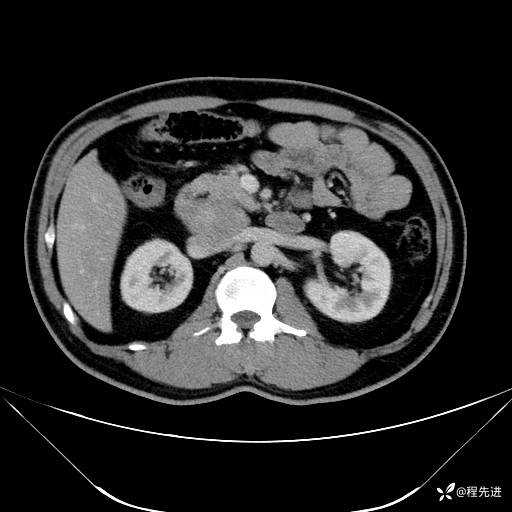

【腹盆】特别精彩病例|发现腹膜后肿物1月余

主诉:发现腹膜后肿物1月余

现病史:患者1月余前查体,行超声检查提示:后腹膜囊实性肿块;慢性胆囊炎伴胆囊内结石;无腹痛腹胀,不伴腹泻发热等;偶感腰背部酸痛。

CT平扫+增强: